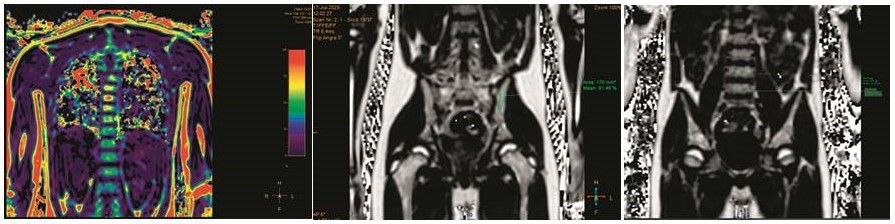

У пациента было проанализировано содержание жира в КМ поясничных позвонков и подвздошных костей. Цветные карты и измерения содержания количества жира в телах позвонков и подвздошных костях представлены на рисунке 4.

Рисунок 4

Цветовое картирование: отмечается смещение цветовой палитры в сторону желто-красного спектра в подвздошных костях, количественное измерение содержания жира: в подвздошных костях – 60%, в теле позвонка L4 – 51%, L5 – 49%

Figure 4

Сolor mapping: yellow to red color spectrum in the iliac bones; the quantitative assessment of bone marrow fat: in the iliac bones – 60%, in the L4 vertebral body – 51%, in the L5 body – 49%

В качестве референсных значений были взяты медианы процентного содержания жировой ткани: 50% для подвздошных костей и 30% для поясничных позвонков, установленные в результате проведенного пилотного исследования группы здоровых добровольцев подросткового возраста [18, 19]. Таким образом, было зафиксировано повышение содержания жировой ткани (фракции жира) в КМ костей таза и поясничных позвонках (L4 и L5).